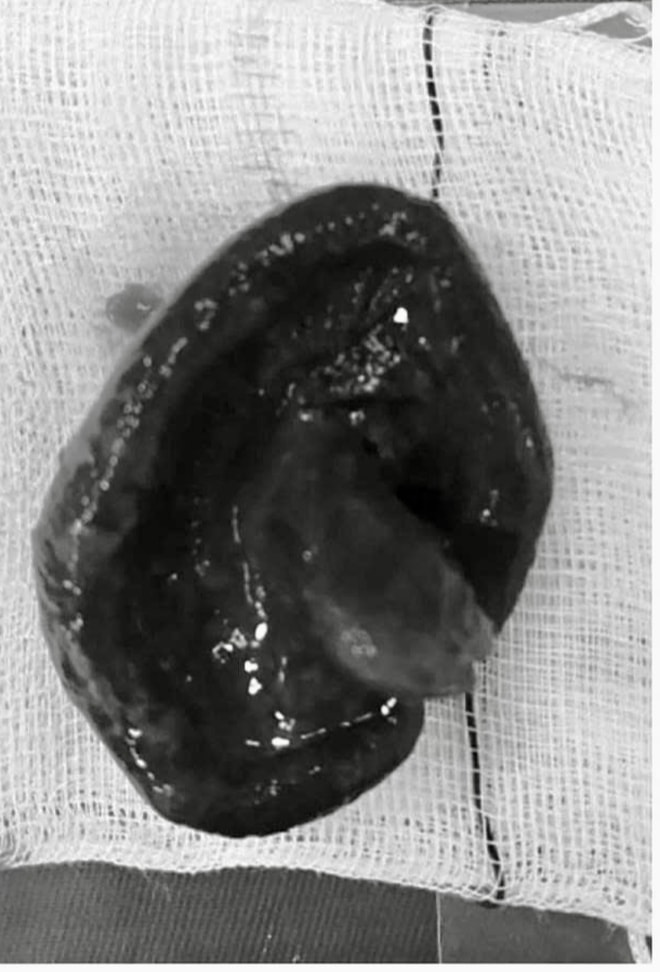

Trường hợp hy hữu khác là của ông L.Đ.D. (SN 1968, trú xã Lệ Thủy) có nguy cơ vỡ ruột vì khối dị vật là cây nấm. Người bệnh cho biết, cách nhập viện khoảng 4 ngày có đi dự tiệc. Quá trình dùng bữa, vô tình nuốt cây nấm mà chưa nhai.

Khi nhập viện, bệnh nhân đau bụng dữ dội kèm nôn mửa, chướng bụng. Qua thăm khám, bác sĩ phát hiện bệnh nhân có đoạn ruột giãn lớn 4cm do dị vật, có nguy cơ vỡ ruột cao. Bệnh nhân được chỉ định phẫu thuật khẩn, quá trình điều trị bác sĩ lấy dị vật gây tắc ruột là cây nấm lớn khoảng 2,5cm.

Ông D. suýt vỡ ruột vì dị vật là cây nấm.